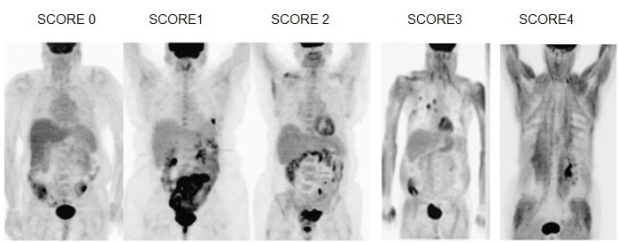

Roy(22) et al. discutem em seu estudo sobre os valores alterados de glicemia e como isso pode influenciar na captação do FGD. Pacientes que apresentam uma glicemia maior que (126 mg/dL) podem apresentar uma redução na sensibilidade do estudo com FDG. Entretanto, pacientes diabéticos que possuem uma glicemia abaixo de (180 mg/dL), apresentam uma biodistribuição adequada do FDG-18F. Os autores classificaram a variação na biodistribuição do FDG em relação à sua captação muscular em diferentes grupos, identificando pontuações entre 0 e 4, demonstrando, portanto, a variação na sensibilidade do método, com o aumento na captação muscular. Na biodistribuição normal, o paciente é identificado com a pontuação 0. Nos casos onde a biodistribuição apresentou alterações, o paciente com captação suave foi identificado com o valor 1; quando a absorção foi muscular, envolvendo mais de um grupo muscular, obteve pontuação 2; nos casos com absorção muscular difusa de intensidade moderada, a pontuação foi 3; e o paciente que apresentou uma absorção muscular difusa e intensa, resultando em exame não diagnosticado, obteve a pontuação máxima que foi 4 (fig. 1). Abaixo, as imagens mostram um exemplo dessa biodistribuição normal e alterada (fig. 2).